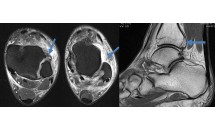

Rupture du ligament calcéno-cuboïdien

La rupture du ligament calcanéo-cuboïdien latéral s'intègre dans le cadre d'une entorse de l'interligne de Chopart qui comprend l'articulation calcanéo-cuboïdienne (ACC) latérale et l'articulation talo-naviculaire, médiale (ATN).